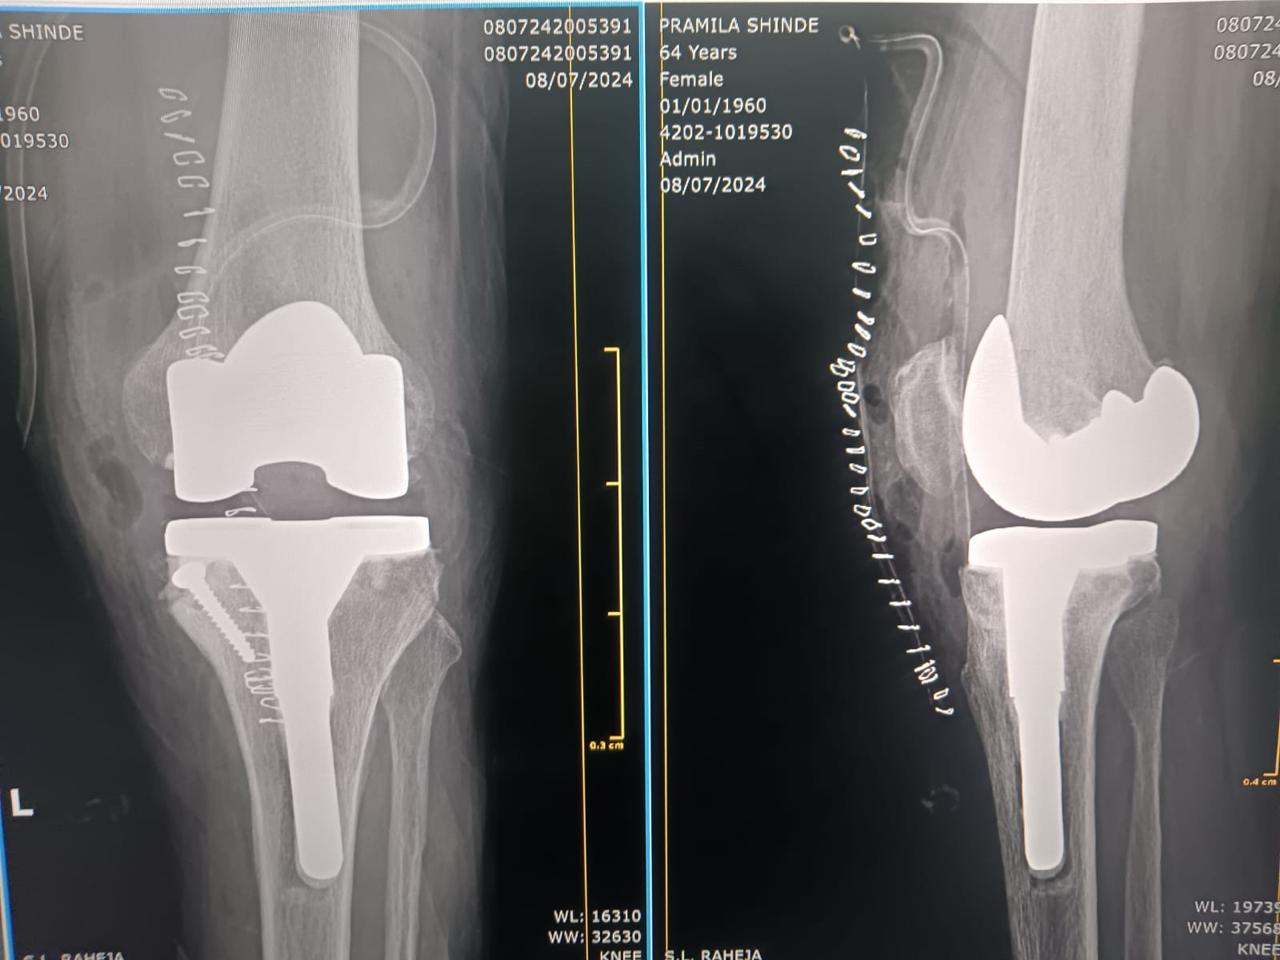

Total knee replacement, also called total knee arthroplasty, is a surgical procedure in which the worn out or damaged surfaces of the knee joint are removed and replaced with an artificial prosthesis.